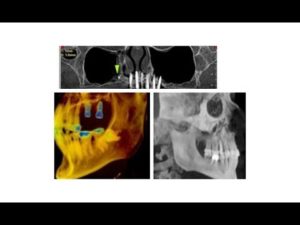

What General Dentists Need to Know about CBCT

By dentists   Posted in Product Information

Posted on June 2, 2017